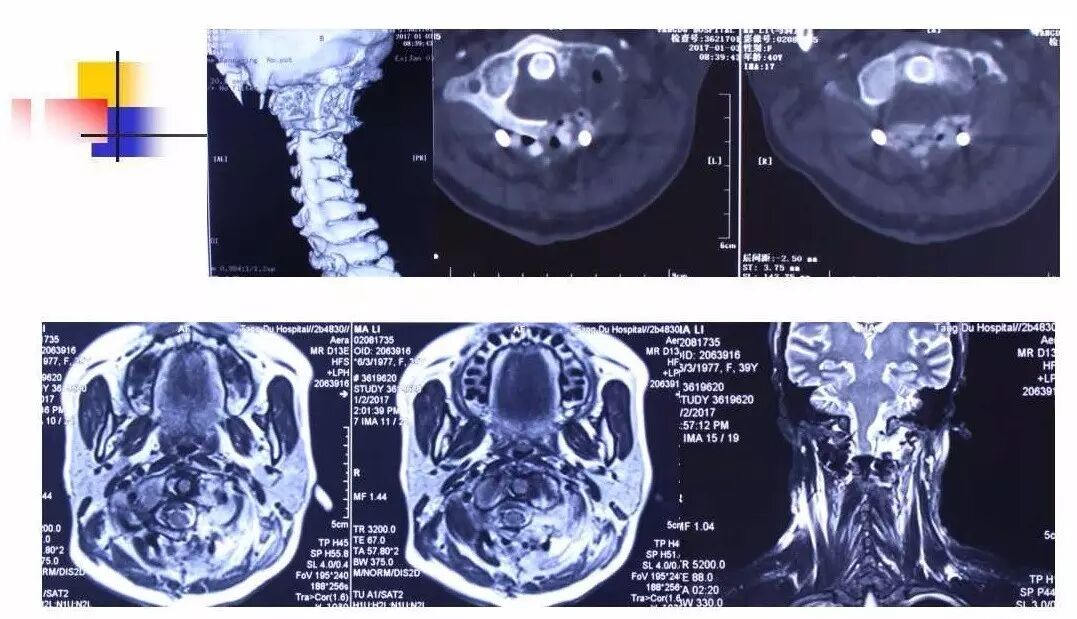

在脊柱神经外科、显微神经外科和颅底肿瘤外科前沿研究和临床诊治领域有着扎实的基础,为全国首批获得脊柱神经外科医师培训认证的神经外科医生。擅长颈椎病、椎管肿瘤及各种脊柱疑难疾病的诊治、脑肿瘤微创手术,尤其擅长颈椎退行性疾病的手术,率先在国内开展了颅底凹陷后路复位、颈前路减压融合等高难度手术,多年来收治了来自全国各地的大量患者,疗效达到国内领先水平。